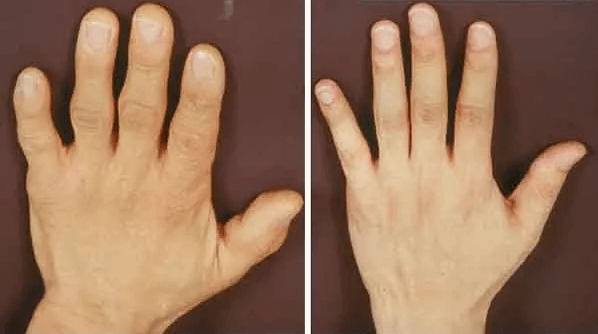

Zde jsou výsledky dosažené některými našimi pacienty:

Tento pacient měl revmatoidní artritidu kolena stupně 1. Jak vidíte, nemoc zmizela beze stopy. Po 5 dnech používání.

Typická kolenní artróza 2. stupně a její úplné vymizení po 7 dnech léčby.

Jedná se o 3. stupeň. Artróza malých prstů. Zotavení po prvním ošetření.